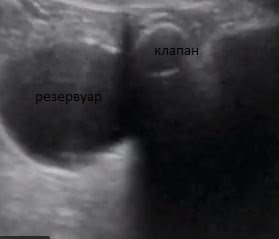

Пациент 1949 г.р., жалобы на периодическое недержание мочи. 10 лет назад прооперирован по поводу аденомы простаты.

Образование остается.

Дивертикул мочевого пузыря? серозоцеле?

смущает гиперэхогенное округлое в полости справа, в верхней части.

Смотрел. Без потоков. В постановке диагноза помог только анамнез.